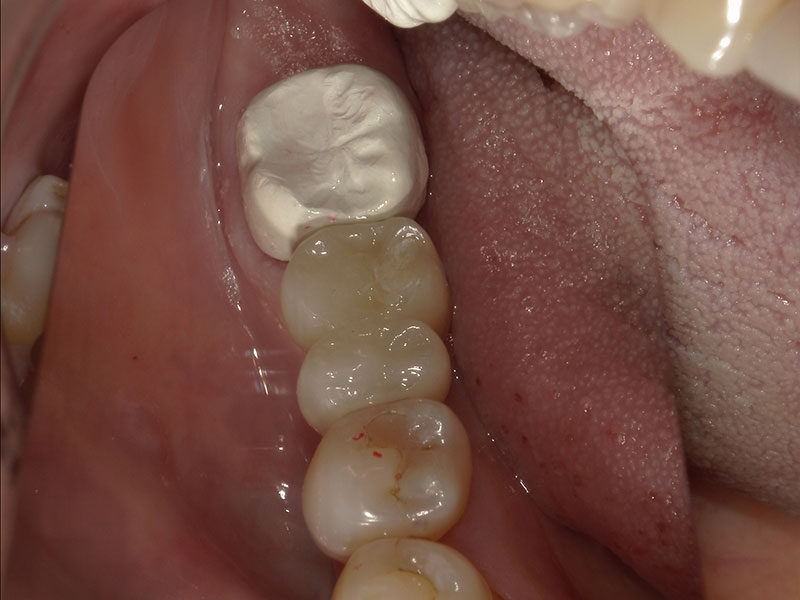

インプラント埋入手術

インプラントの埋入に関しては1回法で行いました。抜歯した部位の骨はしっかりと治癒していました。インプラント埋入後はヒーリングキャップと言ってインプラント周囲の歯茎の形態を整えるためのキャップを装着しました。手術時は特に大きな問題はなく無事に手術が終了しました。